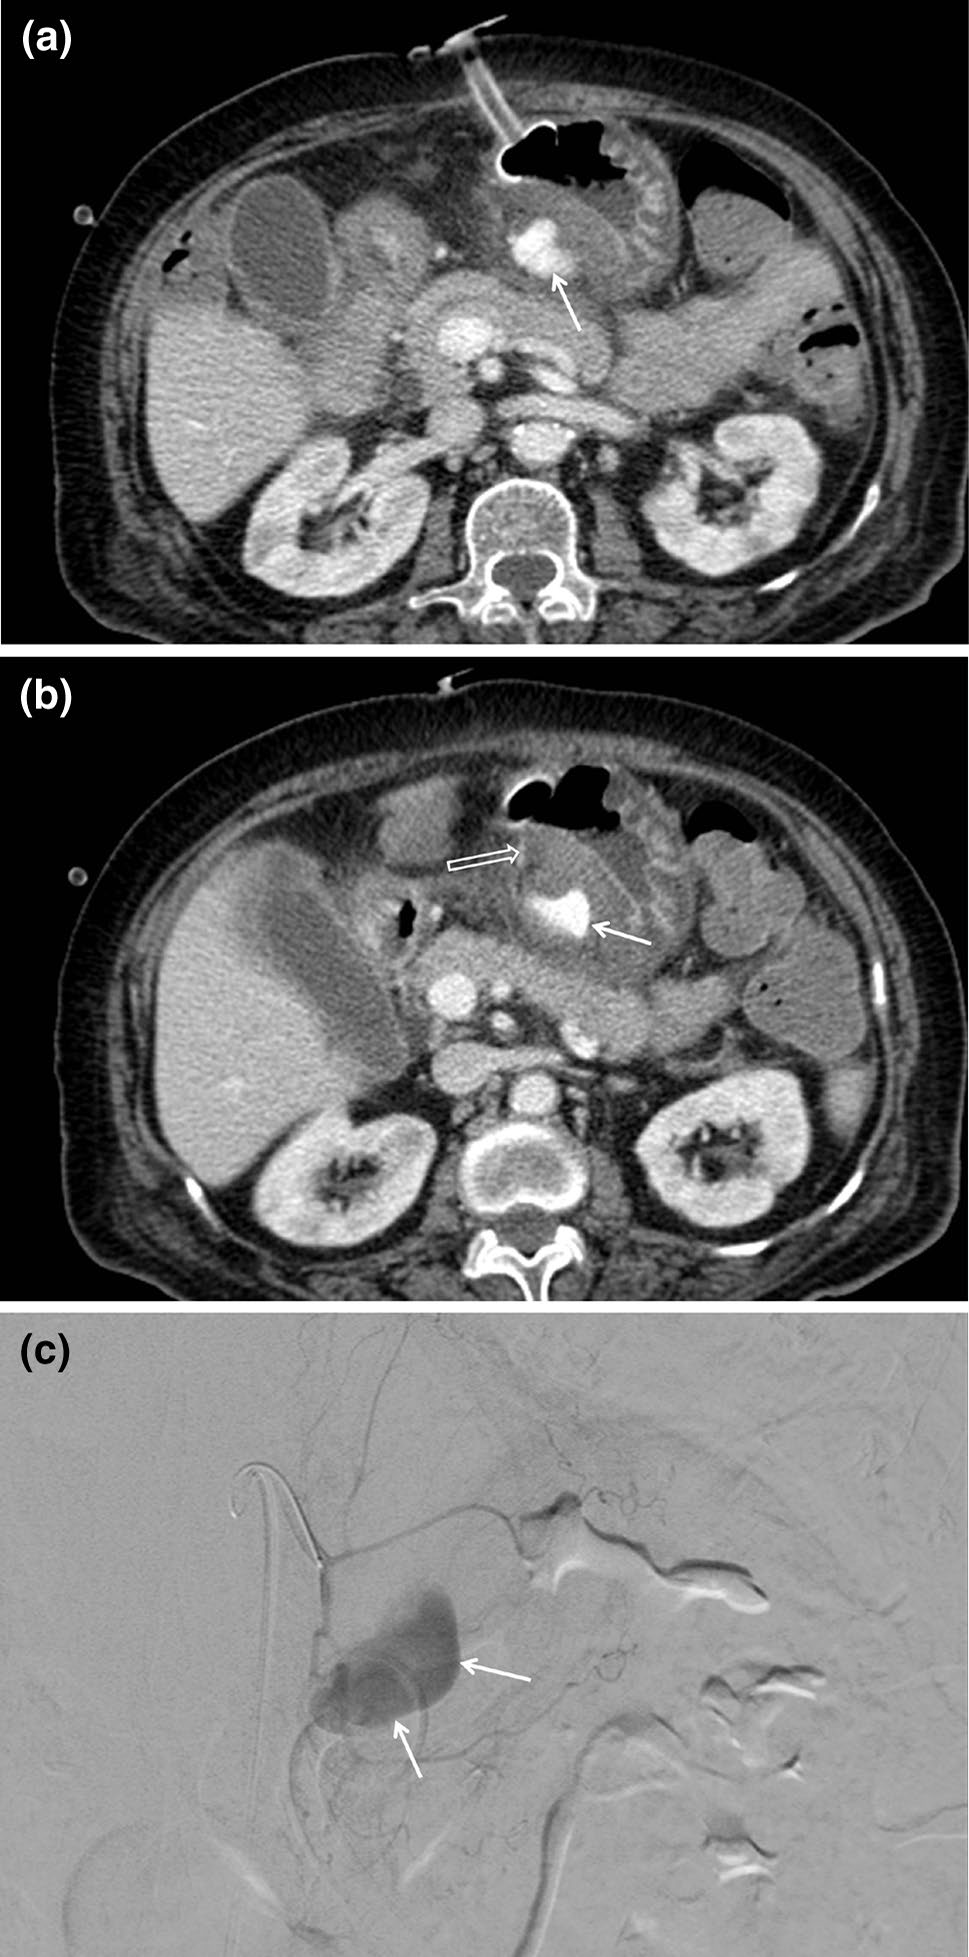

出血

出血可能发生在医疗设备安装期间或移除后不久。大多数腹壁轻微出血可通过压迫处理[14]。然而,一些难治性出血和腹腔内活动性出血的情况仍然是最严重的并发症,需要进行栓塞或手术干预。仅靠腹部X光片无法检测到出血。需使用对比增强多探测器CT是检测出血的一种准确的诊断方法(图22)。